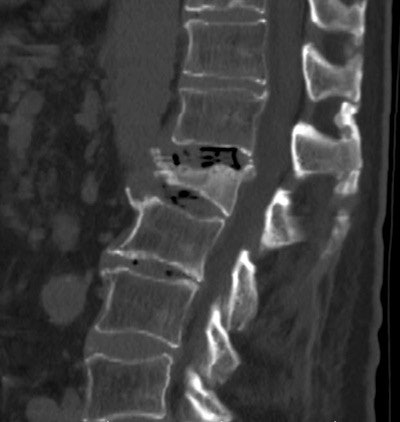

The study evaluated bone mineral density from existing CT scans compared with existing DEXA data in a smaller patient population. The study focused on the L1 vertebrae because it is easily identifiable as the first nonrib-bearing vertebra on thoracic and abdominal scans, Pickhardt said, adding that levels L1 through L5 all were evaluated and showed little variation.

Along with the conventional DEXA exams, CT bone mineral density was measured by choosing a region of interest over vertebral trabecular bone, and measuring Hounsfield units, being careful not to exclude areas that might distort the reading.

Thus, DEXA results applied across the range of CT attenuation results were used to set thresholds that would yield either the 90% sensitivity or 90% sensitivity outcome, or a balance between the two when needed to distinguish osteoporosis from osteopenia. Specifically, an attenuation threshold of 160 HU or less was 90% sensitive, and a threshold of 110 HU was more than 90% specific for distinguishing osteoporosis from osteopenia and normal bone mineral density, the group reported.

CT attenuation values were significantly lower at all vertebral levels for patients with osteoporosis at DEXA (p < 0.001) at the L1 level. Positive predictive values for osteoporosis were 68% or greater at CT attenuation thresholds less than 100 HU; negative predictive values were 99% at thresholds greater than 200 HU, the group reported.

"You can't really talk in terms of accuracy, because it's very hard to compare the DEXA [to CT], but it's pretty clear that when somebody has a 100 HU or lower in the spine, [the patient] is very likely to have osteoporosis, and they might even have a fracture that we can directly see," Pickhardt said. "A lot of these people have been unscreened, or even missed at DEXA, so it's something that radiologists and others need to be aware of."